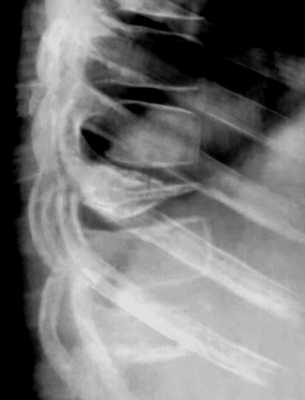

Болезнь Келлера

Болезнь Келлера диагностируется клинически и рентгенологически. Детский ортопед выясняет жалобы и анамнез заболевания, проводит объективный осмотр. Основным методом исследования является рентгенография стопы:

- Болезнь КеллераI. На рентгенограммах вначале отмечается остеопороз ладьевидной кости, вызванный асептическим разрушением ее губчатого вещества. Затем выявляется уплотнение точек окостенения, сплющивание и уплотнение ладьевидной кости. Позже наблюдается дефрагментация ладьевидной кости, т. е. ее распад на отдельные костные фрагменты в результате прогрессирования некротического процесса.

- Болезнь КеллераII. На снимках выявляются патологические изменения в головке пораженной плюсневой кости. В зависимости от срока заболевания может обнаруживаться остеопороз, уплотнение и деформация головки плюсневой кости, ее патологический перелом и дефрагментация.

КТ стопы. Болезнь Келера-2 (остеохондропатия головки 3-й плюсневой кости: снижение высоты головки вследствие остеонекроза, с наличием свободного костно-хрящевого фрагмента).